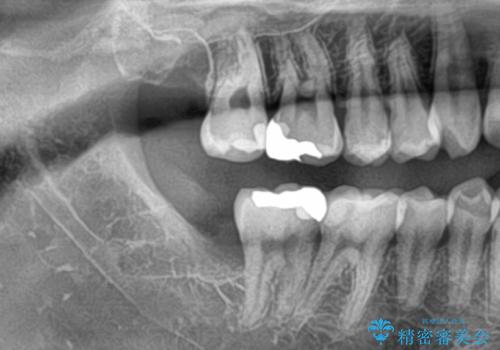

- 親知らずが痛くて抜きたいと来院。

CTを撮影し、神経の位置など確認し安全なことを確認して抜歯を行いました。